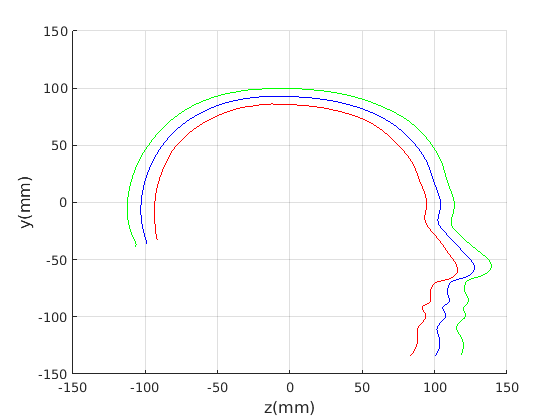

To emphasise the form/shape variation for each of these cases, the mean shape and shapes at mean for the four most significant modes of shape variation are plotted in Fig. 19 and Fig. 20. In this case, ECN normalisation is used.

For the craniofacial sagittal profile model, when not scale-normalised (Fig. 19, left column), the following four dominant shape modes are observed:

-

Cranial height, calvarium convexity and facial angle constitute the main correlated shape variations captured im mode 1, with small cranial heights being correlated with a depression in the region of the bregma. There appears to be a waisting variation where the calvarium alternates between convex (high cranial height) and concave (low cranial height) configurations. Cranial height and ’waisting’ are also strongly correlated with the angle of the face relative to the line between the cranial ellipse centre and nasion.

-

The overall size of the head varies : surprisingly this appears to be almost uncorrelated with craniofacial profile shape. This was only found in the ECN method of pose normalisation.

-

The length of the face varies - there is variation in the ratio of face and cranium size.

4.

Variation in the chin size. A smaller chin appears to be correlated with a more prominent forehead.

The fact that the facial orientation appears to rotate initially led us to suspect a flawed pose normalisation procedure. However, the point about ECN normalisation is that it focuses on aligning the crania rather than faces, using its centre and the nasion, and the face has to follow that normalisation. Thus these results should be interpreted with a fixed cranial ellipse centre and fixed ellipse centre to nasion angle in mind.